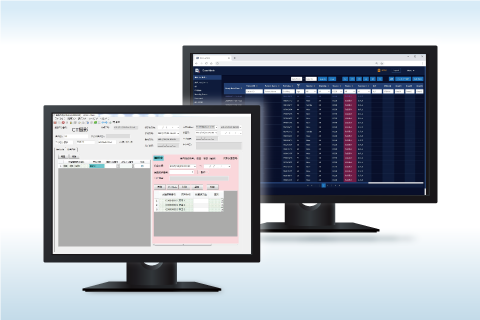

MWM・RIS

MWM・RIS マッチングシステム